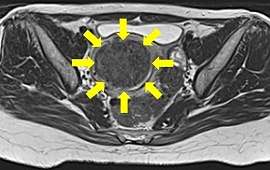

子宮筋腫に対する子宮動脈塞栓術(UAE)の実際

子宮動脈塞栓術(UAE)とは、子宮筋腫に栄養を与えている子宮動脈の血流を止めること

によって、筋腫を縮小させ、筋腫によって生じる過多月経などの症状を改善する治療法

です。足のつけ根に局所麻酔を行い、足のつけ根の動脈にカテーテルを入れ筋腫の近く

まで進めます。カテーテルから塞栓物質を注入し、血管を塞ぎ血流を止めます。塞栓が

完了したらカテーテルを抜き、傷口を押さえて止血します。

血管描出(塞栓前) 血管描出(塞栓後)

塞栓前MRI画像 塞栓後MRI画像